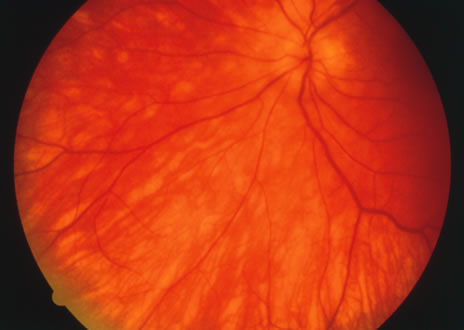

Some patients present with subretinal bands that extend between chorioretinal scars. In addition there may be initial active yellow choroidal lesions that subsequently become atrophic. Vitreous cells are usually present although they may be few and difficult to detect. Visual acuity loss in these cases may be due to active choroidal neovascularization, subretinal bands under the fovea, or from cystoid macular edema. The vast majority of affected patients are women with a mean age of 27 years and both eyes are usually involved. The affected individuals tend to be myopic.49 The age range is from 6 years to 76 years and there is no racial predilection.40 Whether it is a separate disease or a more severe form of multifocal choroiditis is controversial (Figs. 10 and 11). Aggressive therapy is warranted because it has a poorer prognosis than most cases of multifocal choroiditis. This syndrome has been called either diffuse subretinal fibrosis or progressive subretinal fibrosis syndrome.

Fig. 10. A. Fundus photograph showing the subretinal fibrosis extending from the disc to the periphery in a case of diffuse subretinal fibrosis. B. Fundus photograph showing the marked fibrosis in the midperiphery. C. Multifocal choroiditis type lesions noted in the inferior retina.

Fig. 11. A. Subretinal fibrosis in a case of multifocal choroiditis. B. Fellow eye showing classic coalescent hyperpigmented chorioretinal scars of multifocal choroiditis. These scars also can be seen in presumed histoplasmosis syndrome, but the subretinal fibrosis is extremely rare in presumed ocular histoplasmosis syndrome (POHS).